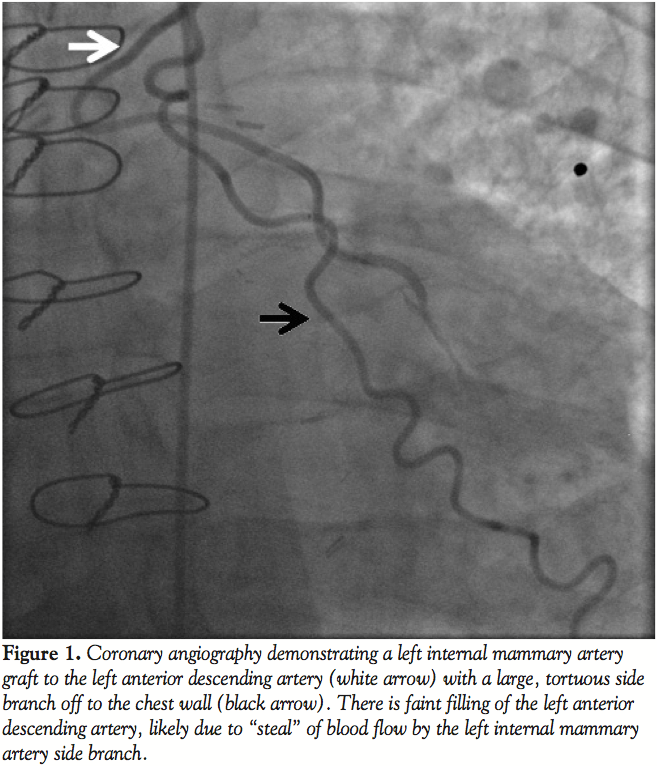

Occlusion of a Left Internal Mammary Artery Graft Side Branch During …